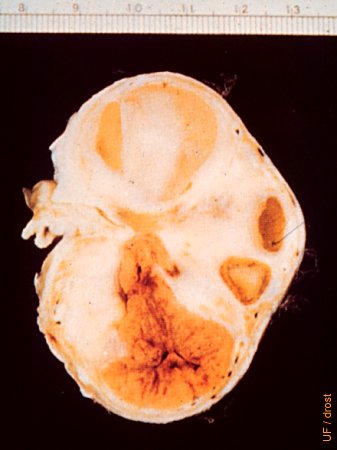

- 成熟黄体图像特征: 通常呈圆形或椭圆形、实质性组织,图像回声均匀,直径可达30-40mm。

- 带中央腔隙的黄体: 一些黄体中心有液性暗区,为黄体腔,并不影响功能,属正常变异。